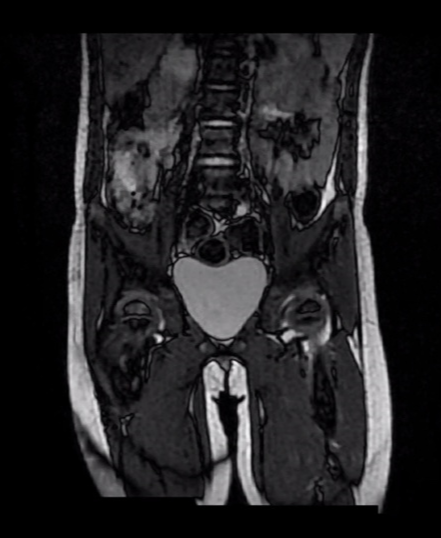

기본적으로 시행하는 x-ray 및 피검사 외에도 MRI 검사를 통해서 고관절 내 농양 형성 여부 및 골수내 침범을 확인하게 됩니다.

- 조금이라도 감염성 고관절의 가능성이 있다면 MRI 검사와 응급수술을 시행한다.